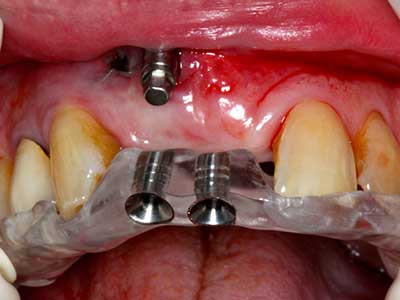

Sollen chirurgische Eingriffe mit unmittelbarer Knochenbeziehung an empfindlichen Strukturen wie Blutgefäßen oder Nerven erfolgen, so bergen rotierende Instrumente ein erhebliches Potential an iatrogener Schädigung. Gerade bei Nervdarstellungen nach iatrogener Schädigung, oder aber im Zuge einer Nervlateralisation für resektive und rekonstruktive Eingriffe oder Implantatinsertionen können piezoelektronische Geräte hilfreich sein Knochendeckel zu präparieren und nervnahe Hartgewebsanteile zu entfernen (Abb. 17-20). Ein leichter Kontakt des Nervstrangs zur Piezospitze bleibt dabei in der Regel folgenlos – allerdings kann eine unvorsichtige Vorgehensweise mit sägeartigen Bewegungen bzw. Ansätzen bei noch vorhandener knöcherner Unterlage durchaus temporäre oder aber auch permanente Nervschädigungen verursachen. Das Risiko einer solchen Schädigung wird jedoch als wesentliche geringer eingeschätzt als unter Anwendung von Säge- oder Fräsinstrumenten (Pereira, Gealh et al. 2014).